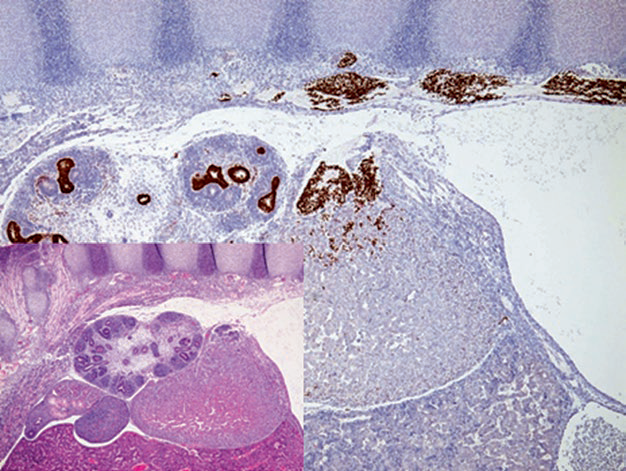

Figure 4. Tissue section of a 12-week embryo, immunohistochemistry with GATA-3 labeling sympathicoblasts in the paravertebral neural crest. These cells migrate into the dorsomedial aspect of the primitive adrenal gland to form the adrenal medulla; GATA-3 also labels urothelium in the renal collecting system.